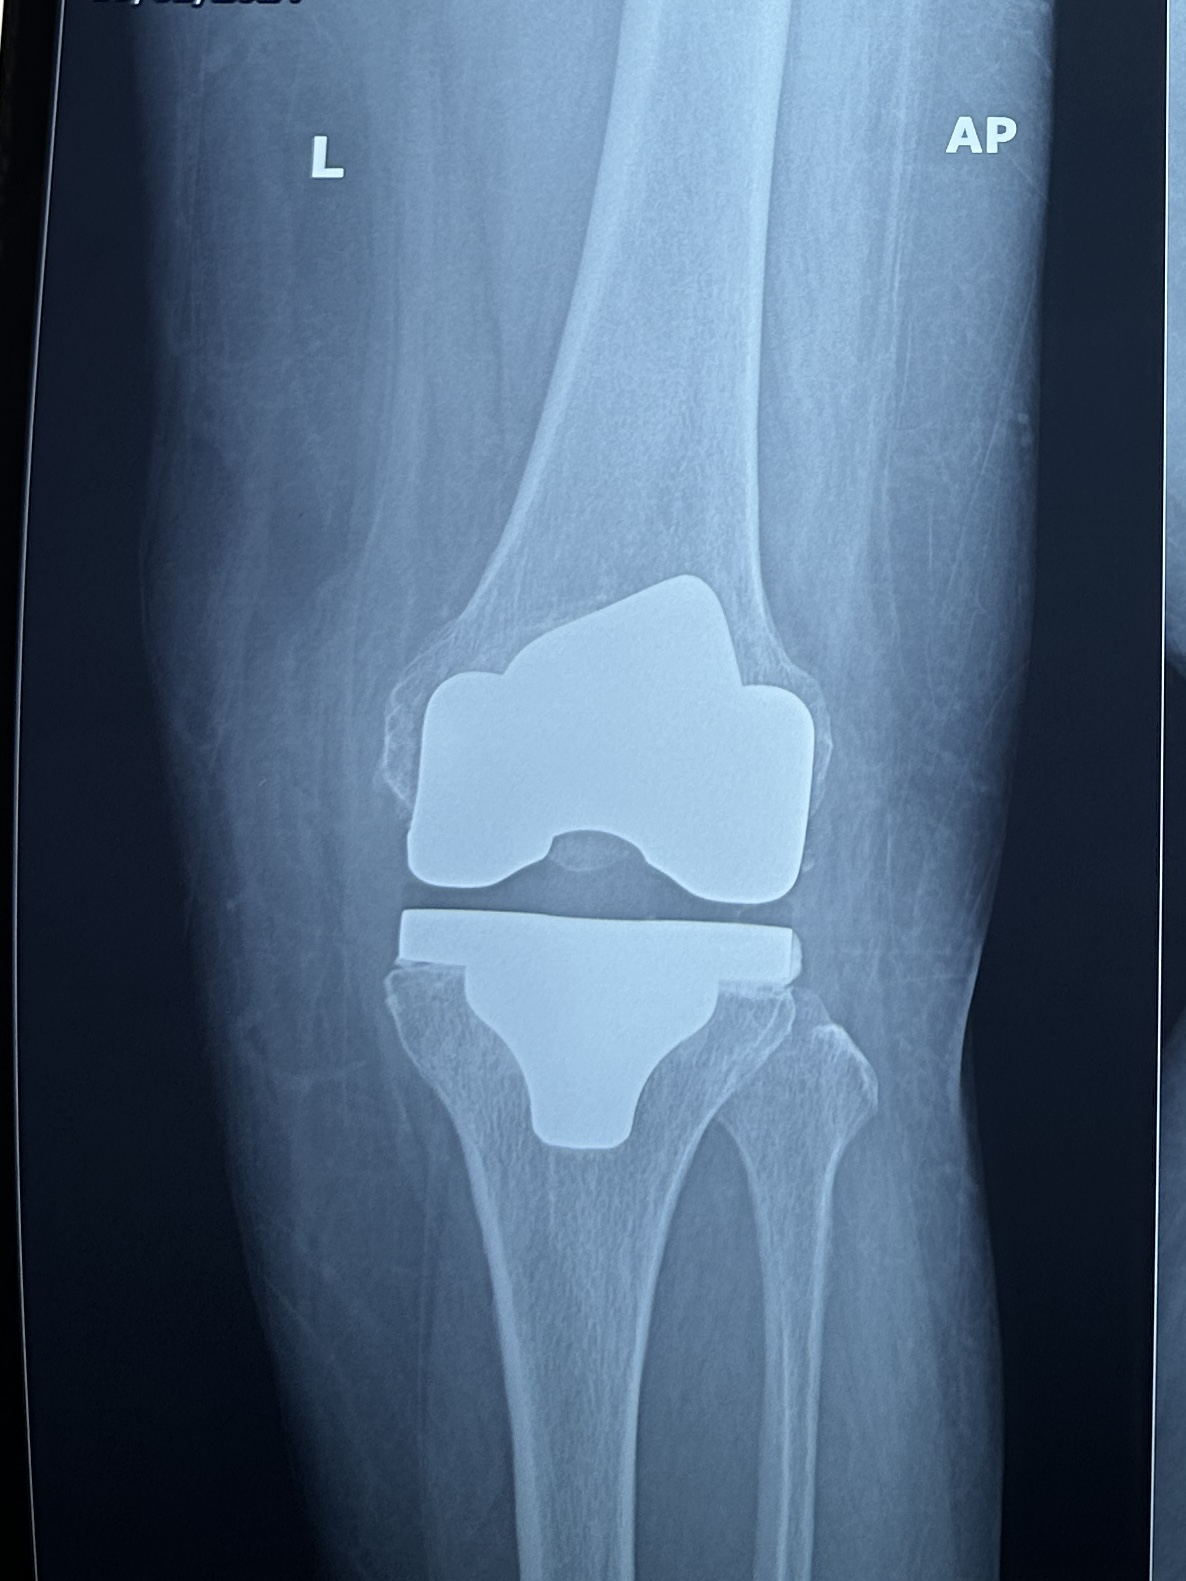

Best Knee Replacement surgeon Total Knee Replacement Minimal invasive procedure Faster recovery High flexion/bending implant